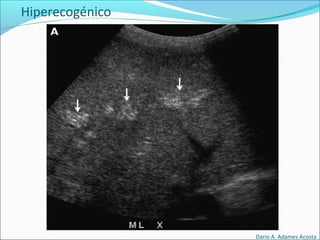

Hiperecogénico

El elemento objetivado es de color mas intenso (mas

blanco) que los elementos circundantes.

Hiperecogénico

Hiperecogénico - sólidos